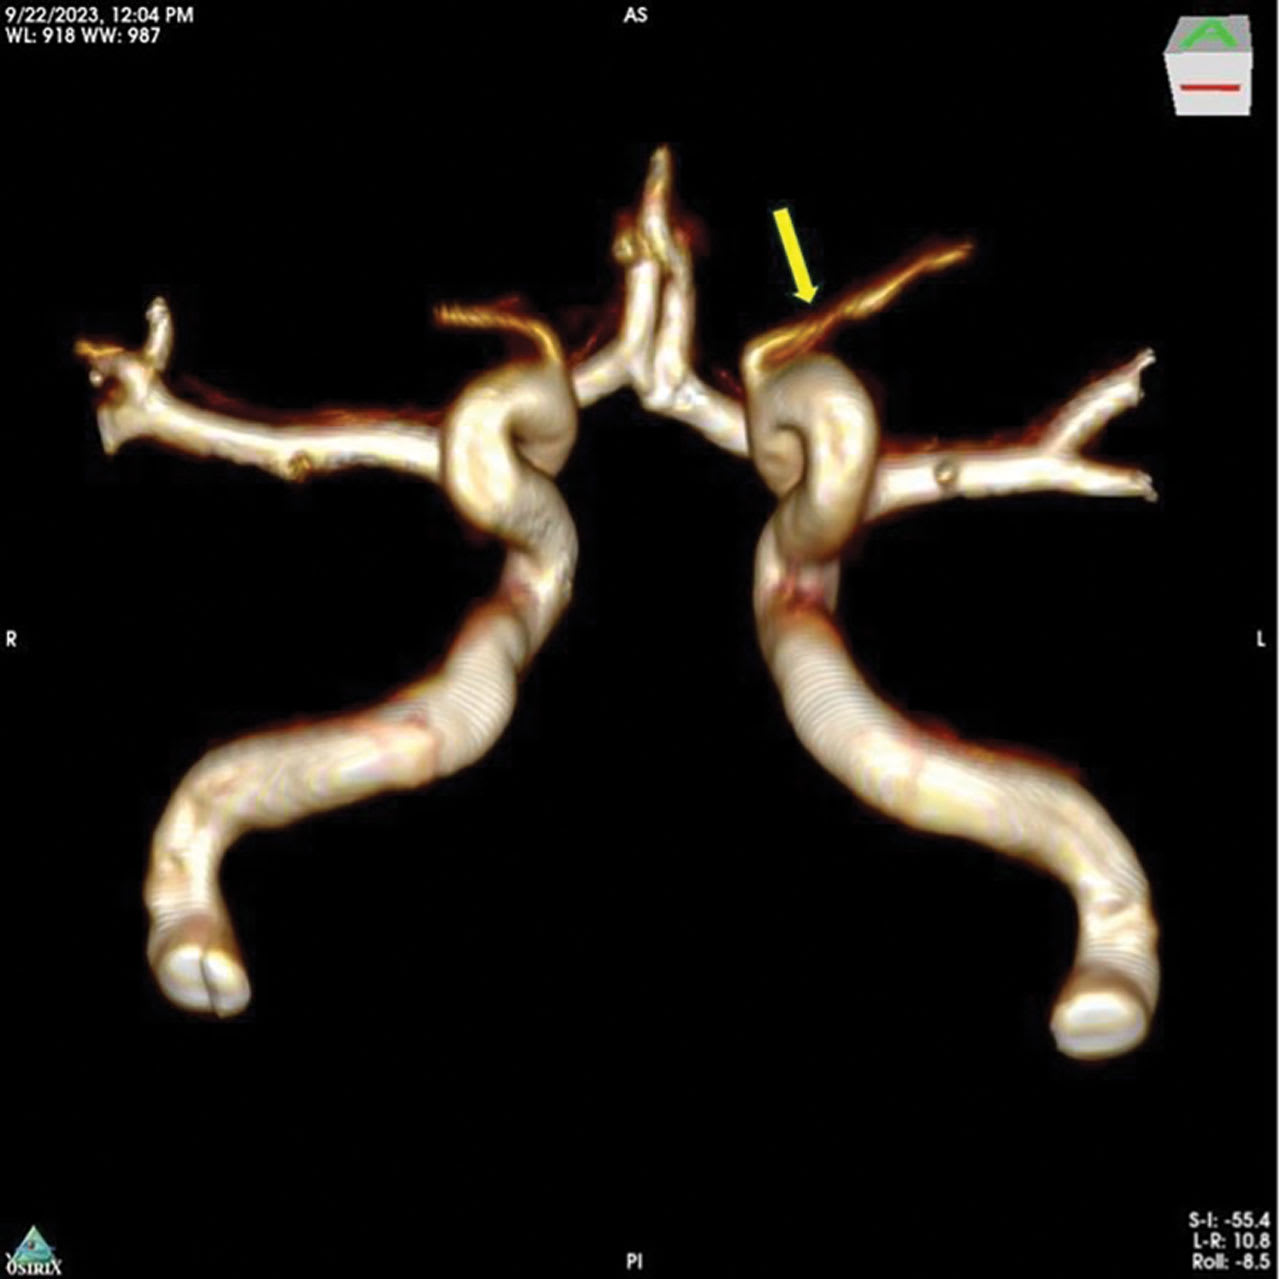

Figure 2. Ophthalmic segment of the left internal carotid artery and ophthalmic artery demonstrating defuse stenosis in the long limb of the ophthalmic artery (between yellow arrows). Three-dimensional rotational angiography image taken with Philips Azurion biplane. Image courtesy OcuDyne.

From an interventional neuroradiology perspective, the presence of OA stenosis was identified via screening MRI angiography (Figure 1) and confirmed with preprocedural digital subtraction angiography (Figure 2). Neurologic evaluations were completed before and after the procedure to monitor the subjects. The procedures were completed by an experienced interventional neuroradiologist under general anesthesia, using standard-of-care vascular access procedures, monitoring, and imaging. The study participants were admitted to the treating facility and observed for 18 to 36 hours after the procedure to ensure recovery and stability.